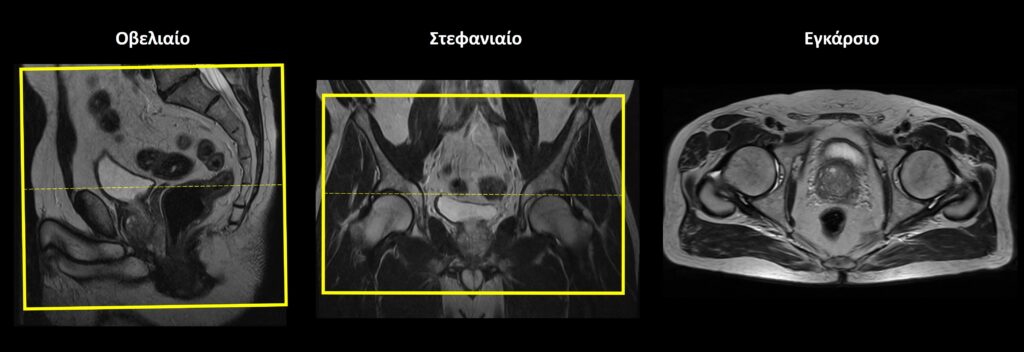

Σχεδιασμός τομών Στατικές Ακολουθίες

Οβελιαίο επίπεδο (Sagittal): οι οβελιαίες τομές σχεδιάζονται κατά μήκος των οργάνων της πυέλου τόσο στο εγκάρσιο όσο και στο στεφανιαίο επίπεδο. Η κλίση των τομών στο εγκάρσιο επίπεδο πρέπει να είναι παράλληλη με τη νοητή γραμμή που ενώνει την ηβική σύμφυση με τον πρωκτικό σωλήνα. Κατάλληλη κλίση πρέπει να δοθεί και στο στεφανιαίο επίπεδο, παράλληλα με το ορθό και τον πρωκτικό σωλήνα. Οι τομές πρέπει να περιλαμβάνουν τα όργανα της πυέλου, από την δεξιά έως την αριστερή κοτύλη.

Εγκάρσιο (Axial/Transversal): οι εγκάρσιες τομές σχεδιάζονται παράλληλα με τις κεφαλές των μηριαίων στο στεφανιαίο επίπεδο και κάθετα στονπρωκτικό σωλήνα στο οβελιαίο επίπεδο. Οι τομές πρέπει να περιλαμβάνουν τα όργανα της πυέλου, από τις λαγόνιες ακρολοφίες (πάνω) έως τον πρωκτό (κάτω).

Σχεδιασμός τομών Δυναμική Ακολουθία

• Οβελιαίο επίπεδο (Sagittal): χρήση μίας μοναδικής τομής πάχους 10-15 mm, η οποία σχεδιάζεται παράλληλα με το ορθό και τον πρωκτικό σωλήνα στο στεφανιαίο επίπεδο. Κατάλληλη κλίση πρέπει να δοθεί και στο εγκάρσιο επίπεδο, παράλληλα με τη νοητή γραμμή που ενώνει την ηβική σύμφυση με τον πρωκτικό σωλήνα. Επίσης, η τομή πρέπει να τοποθετηθεί στη μέση του ορθού και του πρωκτού.